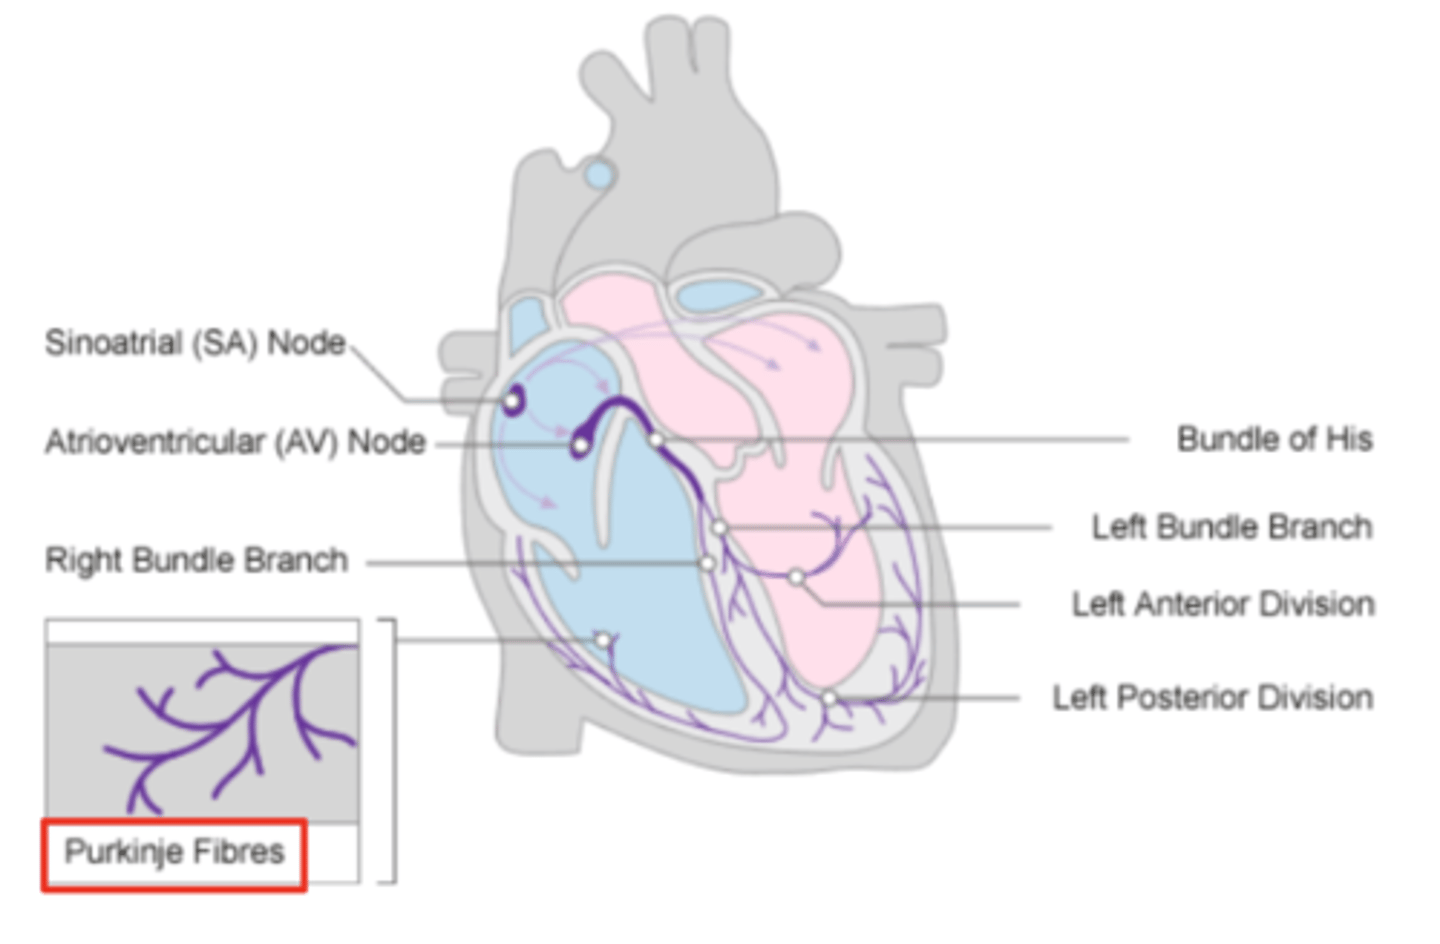

Purkninje fibers

Describe the propagation of waves in the conduction system ?

. Reaches Purkinje fibers in the walls of the ventricles

What role does the moderator band play in the conduction system?

Allows the wave to reach the papillary muscles, inducing their contraction simultaneously with that of the ventricles.

REMEMBER: PAPILLARY MUSCLES ACT THROUGH THE CHORDAE TENDINAE TO CONTROL THE TRICUSPID AND MITRAL VALVES.

What are the Purkinje fibers, and what is their function?

specialized conductive fibers in the walls of the ventricles that

facilitate rapid transmission of electrical impulses,

ensuring efficient and synchronized ventricular contraction.